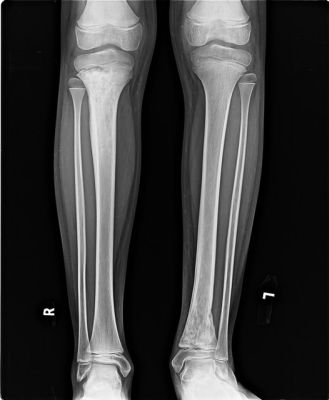

We do all X-Ray procedures like :

- Routine X-Rays are done without appointment also.